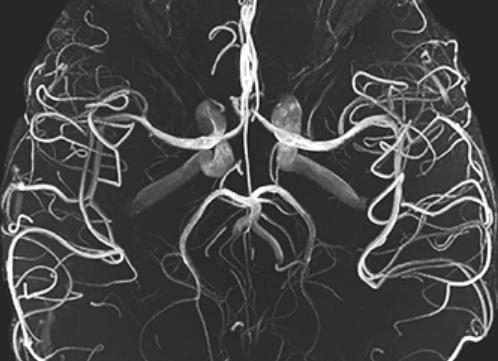

Ангиография мрт сосудов головного мозга

Что это — МРТ ангиография сосудов головного мозга? С ее помощью можно подробно увидеть мозговые артерии, их форму, размеры, отношение к окружающей ткани мозга.

Отдельно выделяют МРТ ангиографию сосудов головного мозга с контрастом. Ее суть заключается в введении специального вещества, который окрашивает мозговые артерии. Он более информативен, чем обычная МРТ.

Современная ангиография, которая проводится для исследования сосудов в мозге, характеризуется особым принципом воздействия. Суть процедуры и получения результата основана на влиянии высоких частот окружающего электромагнитного поля. По результатам проведенного обследования врач и пациент получает возможность исследовать сосуды головного мозга и шеи, общего характера кровотока в них. Именно получение объемного изображение артерий и вен, ангиография отличается от обычного МРТ.